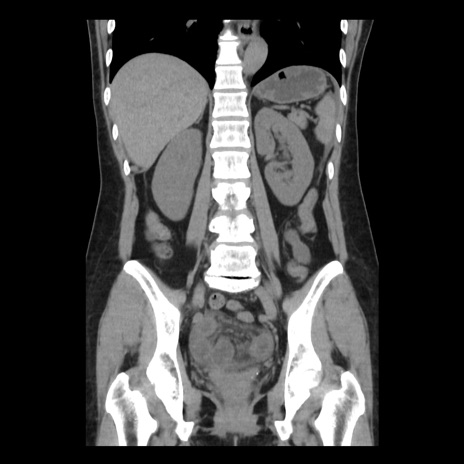

症例10(冠状断像)

【症例】 50歳代女性

【主訴】 腹痛

【現病歴】前日生レバーを食べた。今朝に排便あり。 昼前に突然発症の腹痛を生じ、当院救急外来を受診した。

【既往歴】 子宮筋腫にてで子宮全摘後

【身体所見】 意識清明、腹部:平坦、軟、下腹部やや左を中心に圧痛・反跳痛あり、筋性防御あり

【データ】WBC 7800、CRP 0.07